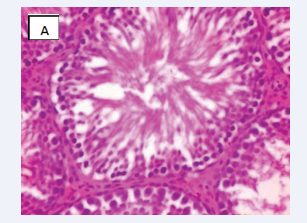

Photomicrograph of testicular section stained by Haematoxylin and Eosin (×400) (Figure 3-6).

Figure 3 CONTROL A-Normal testicular architecture with normal seminiferous tubules and insterstitial spaces contains normal leydig cells

Figure 3: CONTROL A-Normal testicular architecture with normal seminiferous tubules and insterstitial spaces contains normal leydig cells

Testicular architecture was averagely normal in the group exposed to 10 mg/kg of bisphenol A, but interstitial spaces plus leydig vessels were clogged and few normal seminiferous tubular structure, indicating fairly normal testicular structure. All other groups displayed normal testicular architecture, and achieved healthy developmental stages. Both the sertoli and sperm cells are healthy having spermatozoa present in their lumen. This is consistent with a mouse study that found bisphenol A injection to damage testis shape, particularly the size of seminiferous tubules and the epithelium, which were both greatly reduced and showed various phases of spermatogenesis impairment [18].